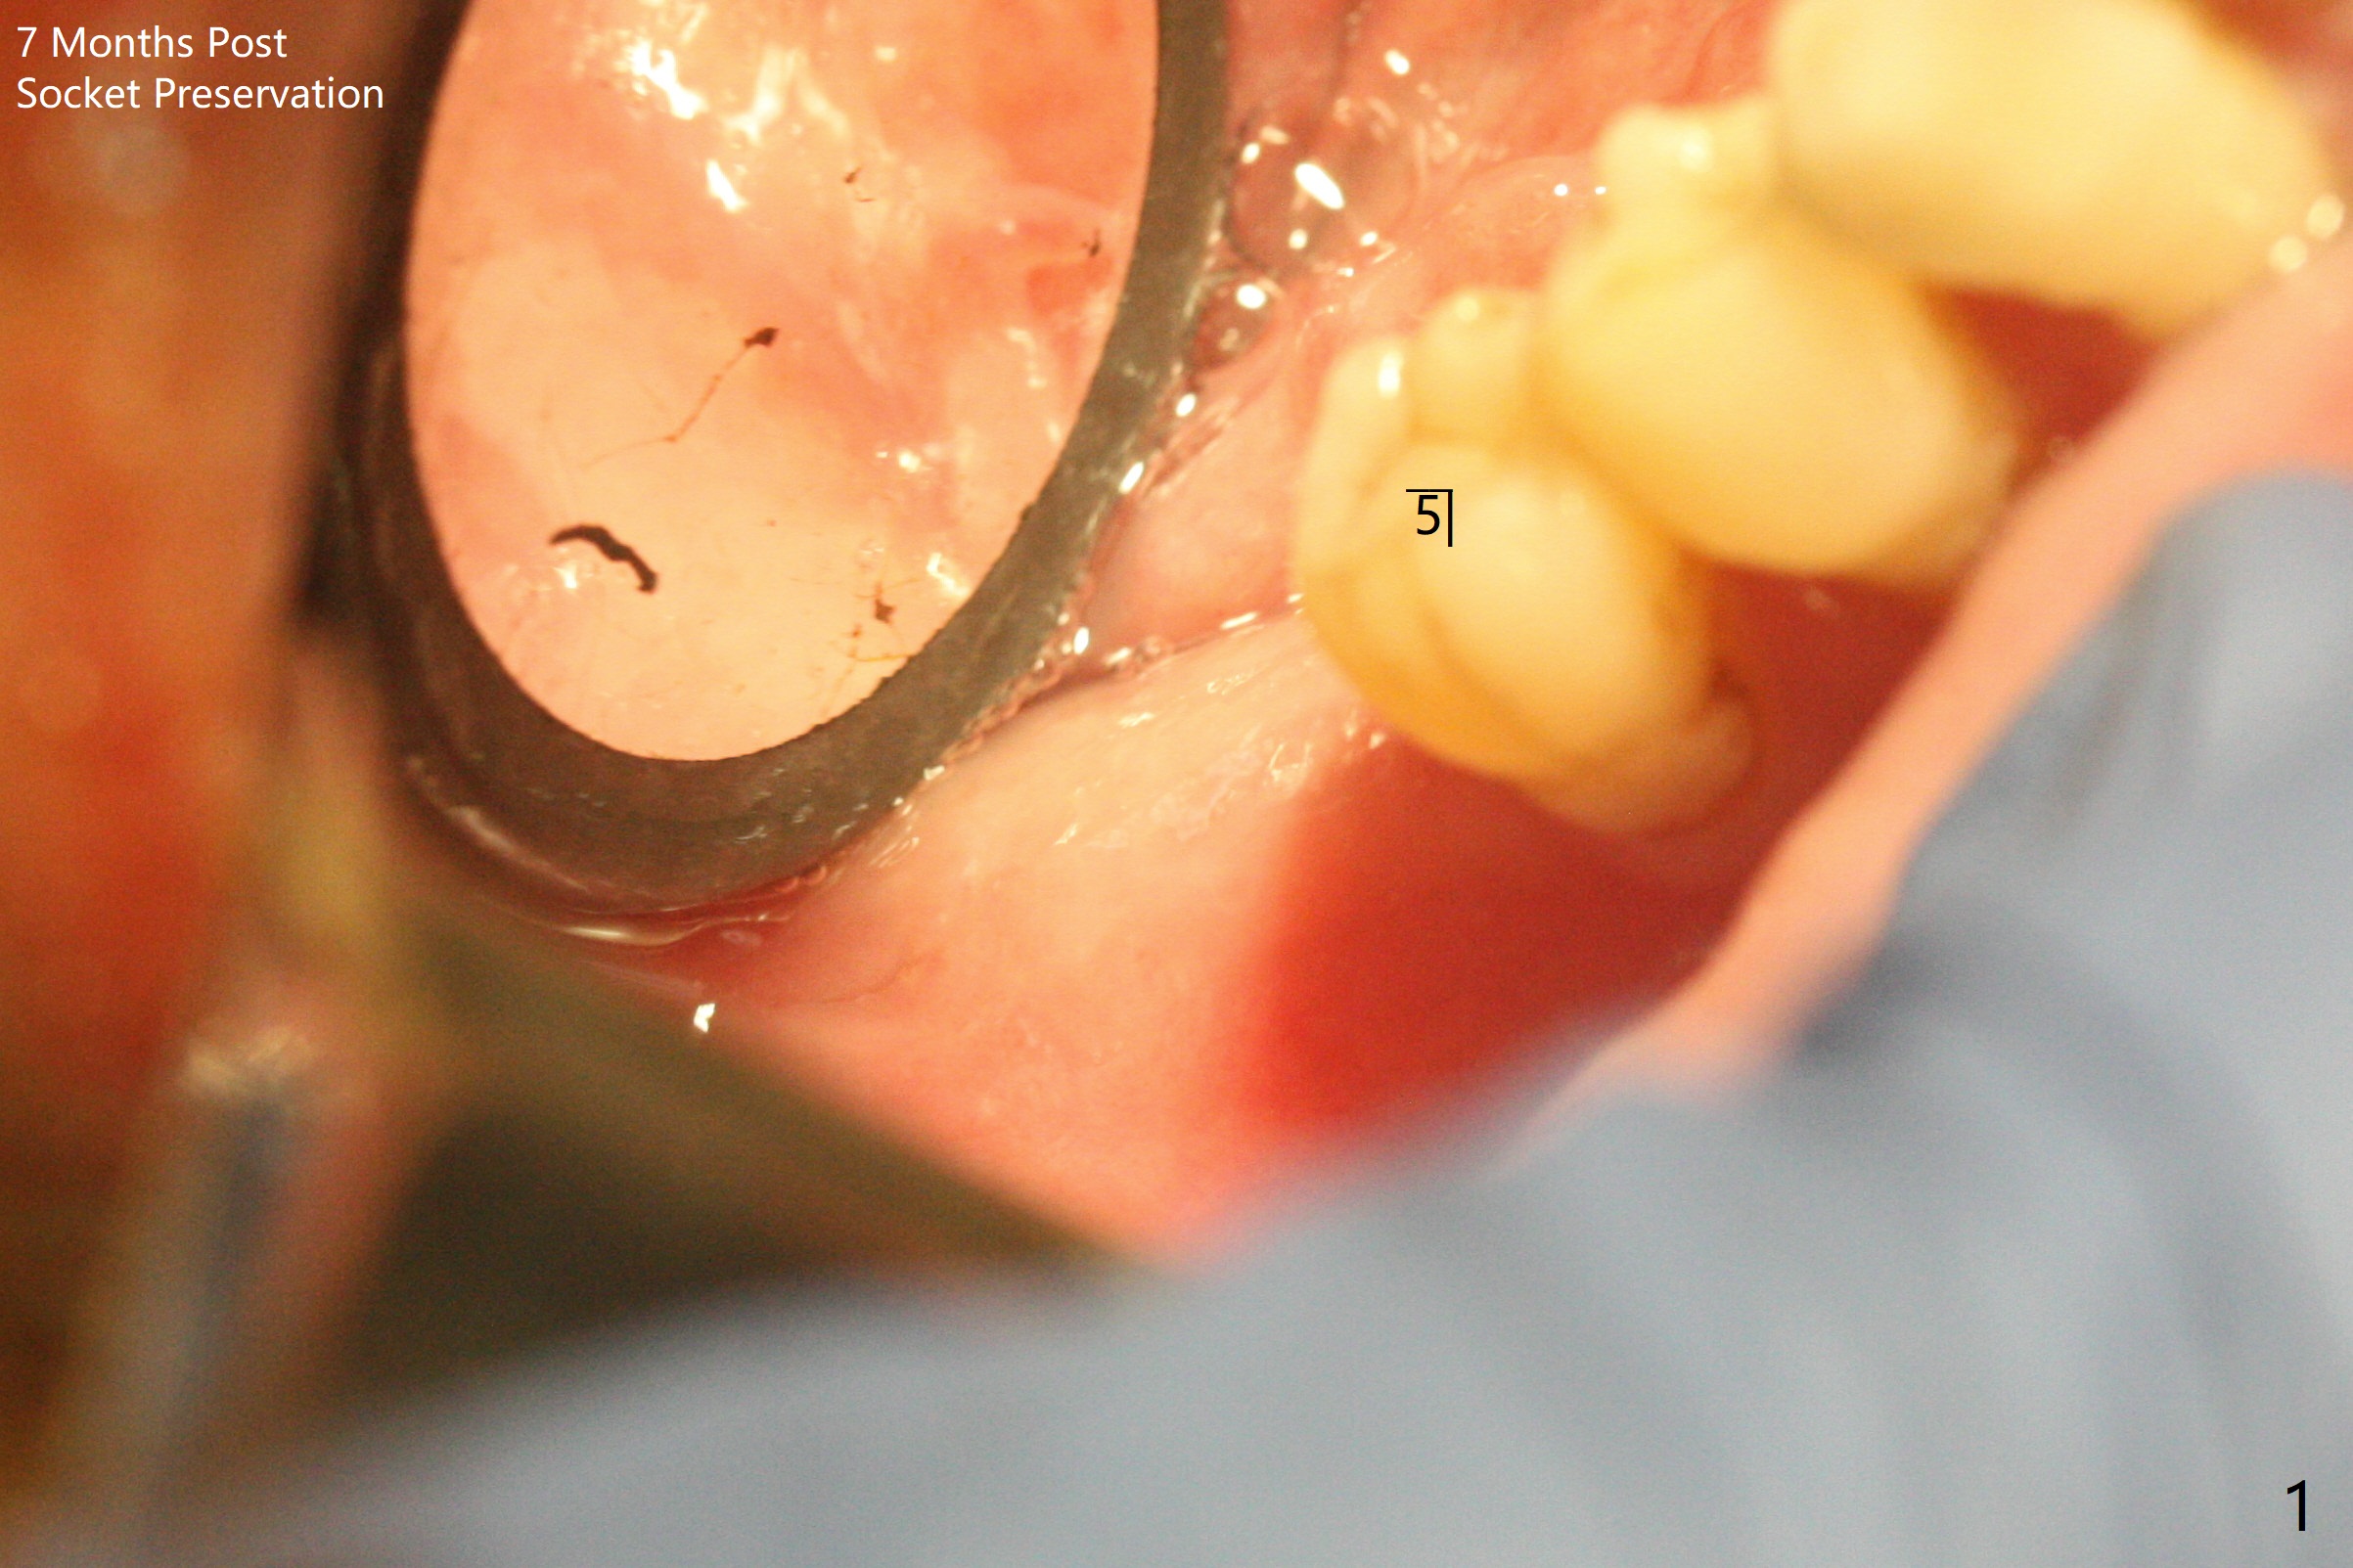

54岁男,右下6,7位点保留后7个月回来植牙,植牙床是个平面(图一),今后两个牙齿之间龈乳头一定缺乏,如何重建?放置导板,稍微使用环形钻头,在6,7植牙床上形成标记(图二),然后切开,植入植体,6扭力低,7高,所以安置愈合(6x5毫米)和修复(5.5x4(4)毫米)基台。原来导板设计把植体植入牙槽嵴(图三:白虚线)下1-2毫米,自动提高植体间牙槽嵴,接着把钻洞产生的骨粉放在后者上缘(*),由近中和远中基台固定。最后覆盖胶原膜,缝合(图四)。原来导板需要切除的角化龈保留住了(图四:7B,7L)。放入修复基台目的是利用它的高度固定牙周敷料。术后3个月7牙槽窝愈合(位点保存后10个月,图五:*),植体间牙槽嵴仍旧高(箭头),6放置修复基台,准备做临时牙冠。右上7反合,需要做局部矫正(图六)。病人非常感激术后三个月制作的临时牙冠(连体)。术后五个月对临时牙冠进行修改:6牙合面垫高(图七:*),这样上下7牙合面分开,上7颊侧放置矫正器,下7牙圈(舌侧有cleat),两者之间安置橡皮筋,上7就可以自由往舌侧移动。术后8.5个月全景片和CT显示植体种植牙槽嵴下(图八至十),这也是重建龈乳头基础。